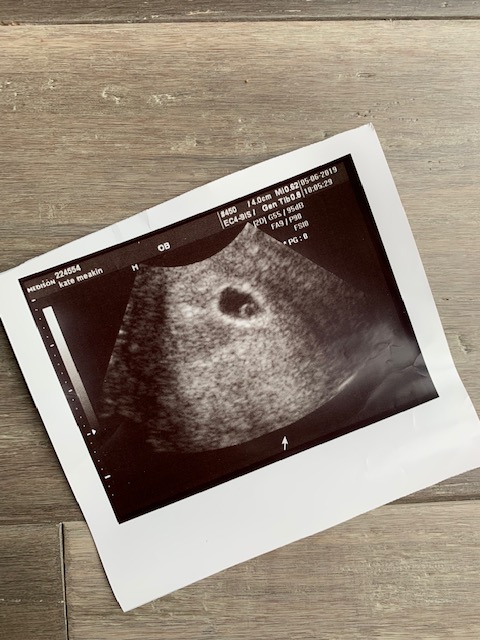

We reached the 5 week mark and this was big for us. Then out of nowhere, I started spotting. There was no pain and it was brown blood so initially I didn’t feel too worried. Neither were the clinic. The next few days passed and the spotting would come and go so we asked for an early scan for some reassurance. I was 5 weeks 5 days when we went in and we had no idea what we would see. My clinic don’t like to scan before 7 weeks especially as this can induce more anxiety and worry if the dates don’t match up to what you see on the ultrasound. But to our surprise and relief we saw one beautiful little embryo sac.

Baby Meakin. We were due in January.

The love was instant. Just like when I saw Austins first ultrasound. Was this our triple rainbow baby? I think Mr M may have even shed a little tear when he looked at the screen. Our consultant was happy with the position of the pregnancy, located away from a threatened miscarriage and he could see no signs of a bleed or where the spotting may be coming from. There were no guarantees but at this stage everything looked good.

Our little poppy seed photo sat proudly on my bed side table that night and I went to sleep with a protective hand resting on my swollen tummy.